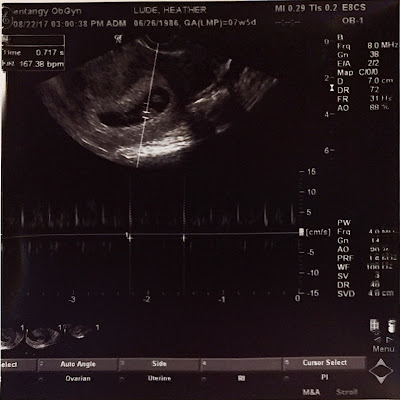

Later in the afternoon we had our first appointment with the OB.  Bran and Joe were able to come to the appointment to see the new little peanut's first ultrasound. Everything looks great and baby is measuring on track for an April 5 due date. Bran was so incredibly cute at the appointment!  He was so excited to watch and kept saying "baby!". Dr. Turner was talking to him and said okay Bran here comes the heartbeat, it is going to sound like a train.  As soon as he heard it he started going "choo choo". I think my heart melted.  Brannock is going to be the best big brother (even if he really has no clue what is going on right now). The baby's HR is faster than Bran's first ultrasound HR, 167 BPM.

Tiny little heartbeat. 167 BPM.